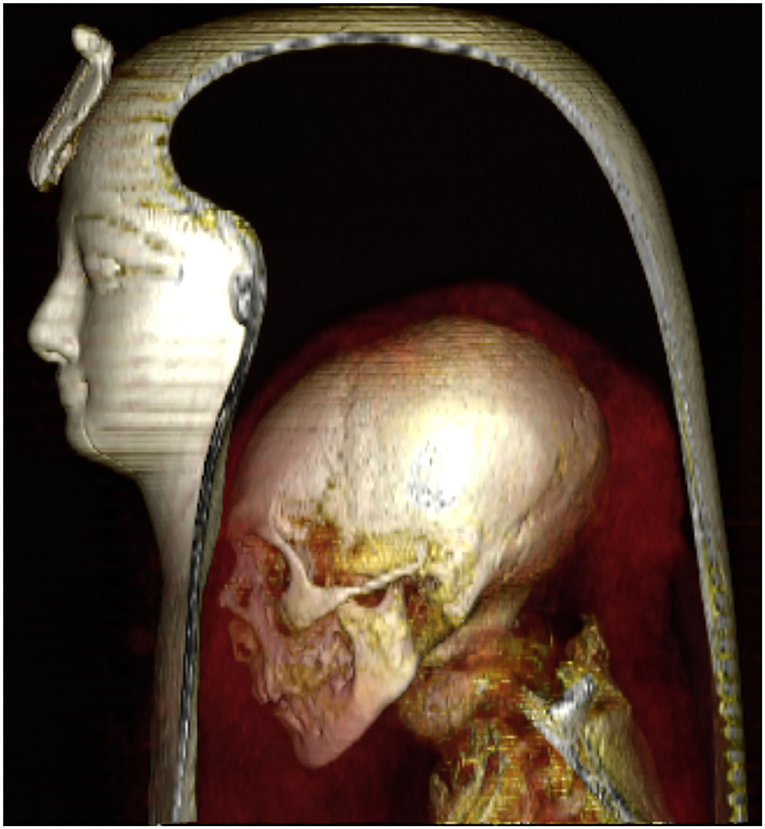

Gracias a una tomografía es que ahora podemos saber cómo se ve la momia del faraón Amenhotep I, quien gobernó, más o menos, desde 1525 hasta 1504 a.C. Sí, su sarcófago se descubrió hace unos 140 años, cerca de la ciudad de Luxor, en Egipto, pero es hasta ahora que podemos conocer su rostro.

Así se ve la momia del faraón Amenhotep I gracias a una tomografía

Comencemos por explicarles que los arqueólogos no querían abrir el sarcófago para preservar la mascara funeraria y vendajes de la momia del faraón Amenhotep I, por lo que decidieron realizarle una tomografía para conocer más o menos como era este personaje histórico.

No fue solo una tomografía, sino varias con las que los arqueólogos descubrieron varias cosas que hasta ahora desconocían del faraón y de su entierro. Por ejemplo, lograron saber como era su rostro, el cual había estado envuelto durante miles de años, informaron en el estudio que se publicó en la revista Frontiers in Medicine.

Al respecto, también la doctora Sahar Saleem, profesora de radiología en la Facultad de Medicina de la Universidad de El Cairo y principal autora del estudio, dijo a la BBC que lo que más llamó su atención fue ver los rasgos faciales del faraón, los cuales, de acuerdo a la experta, se parecen mucho a los de su padre, Ahmose I, el primer faraón de la dinastía XVIII de Egipto: un mentón estrecho, nariz pequeña y estrecha, cabello rizado y dientes superiores ligeramente protuberantes.